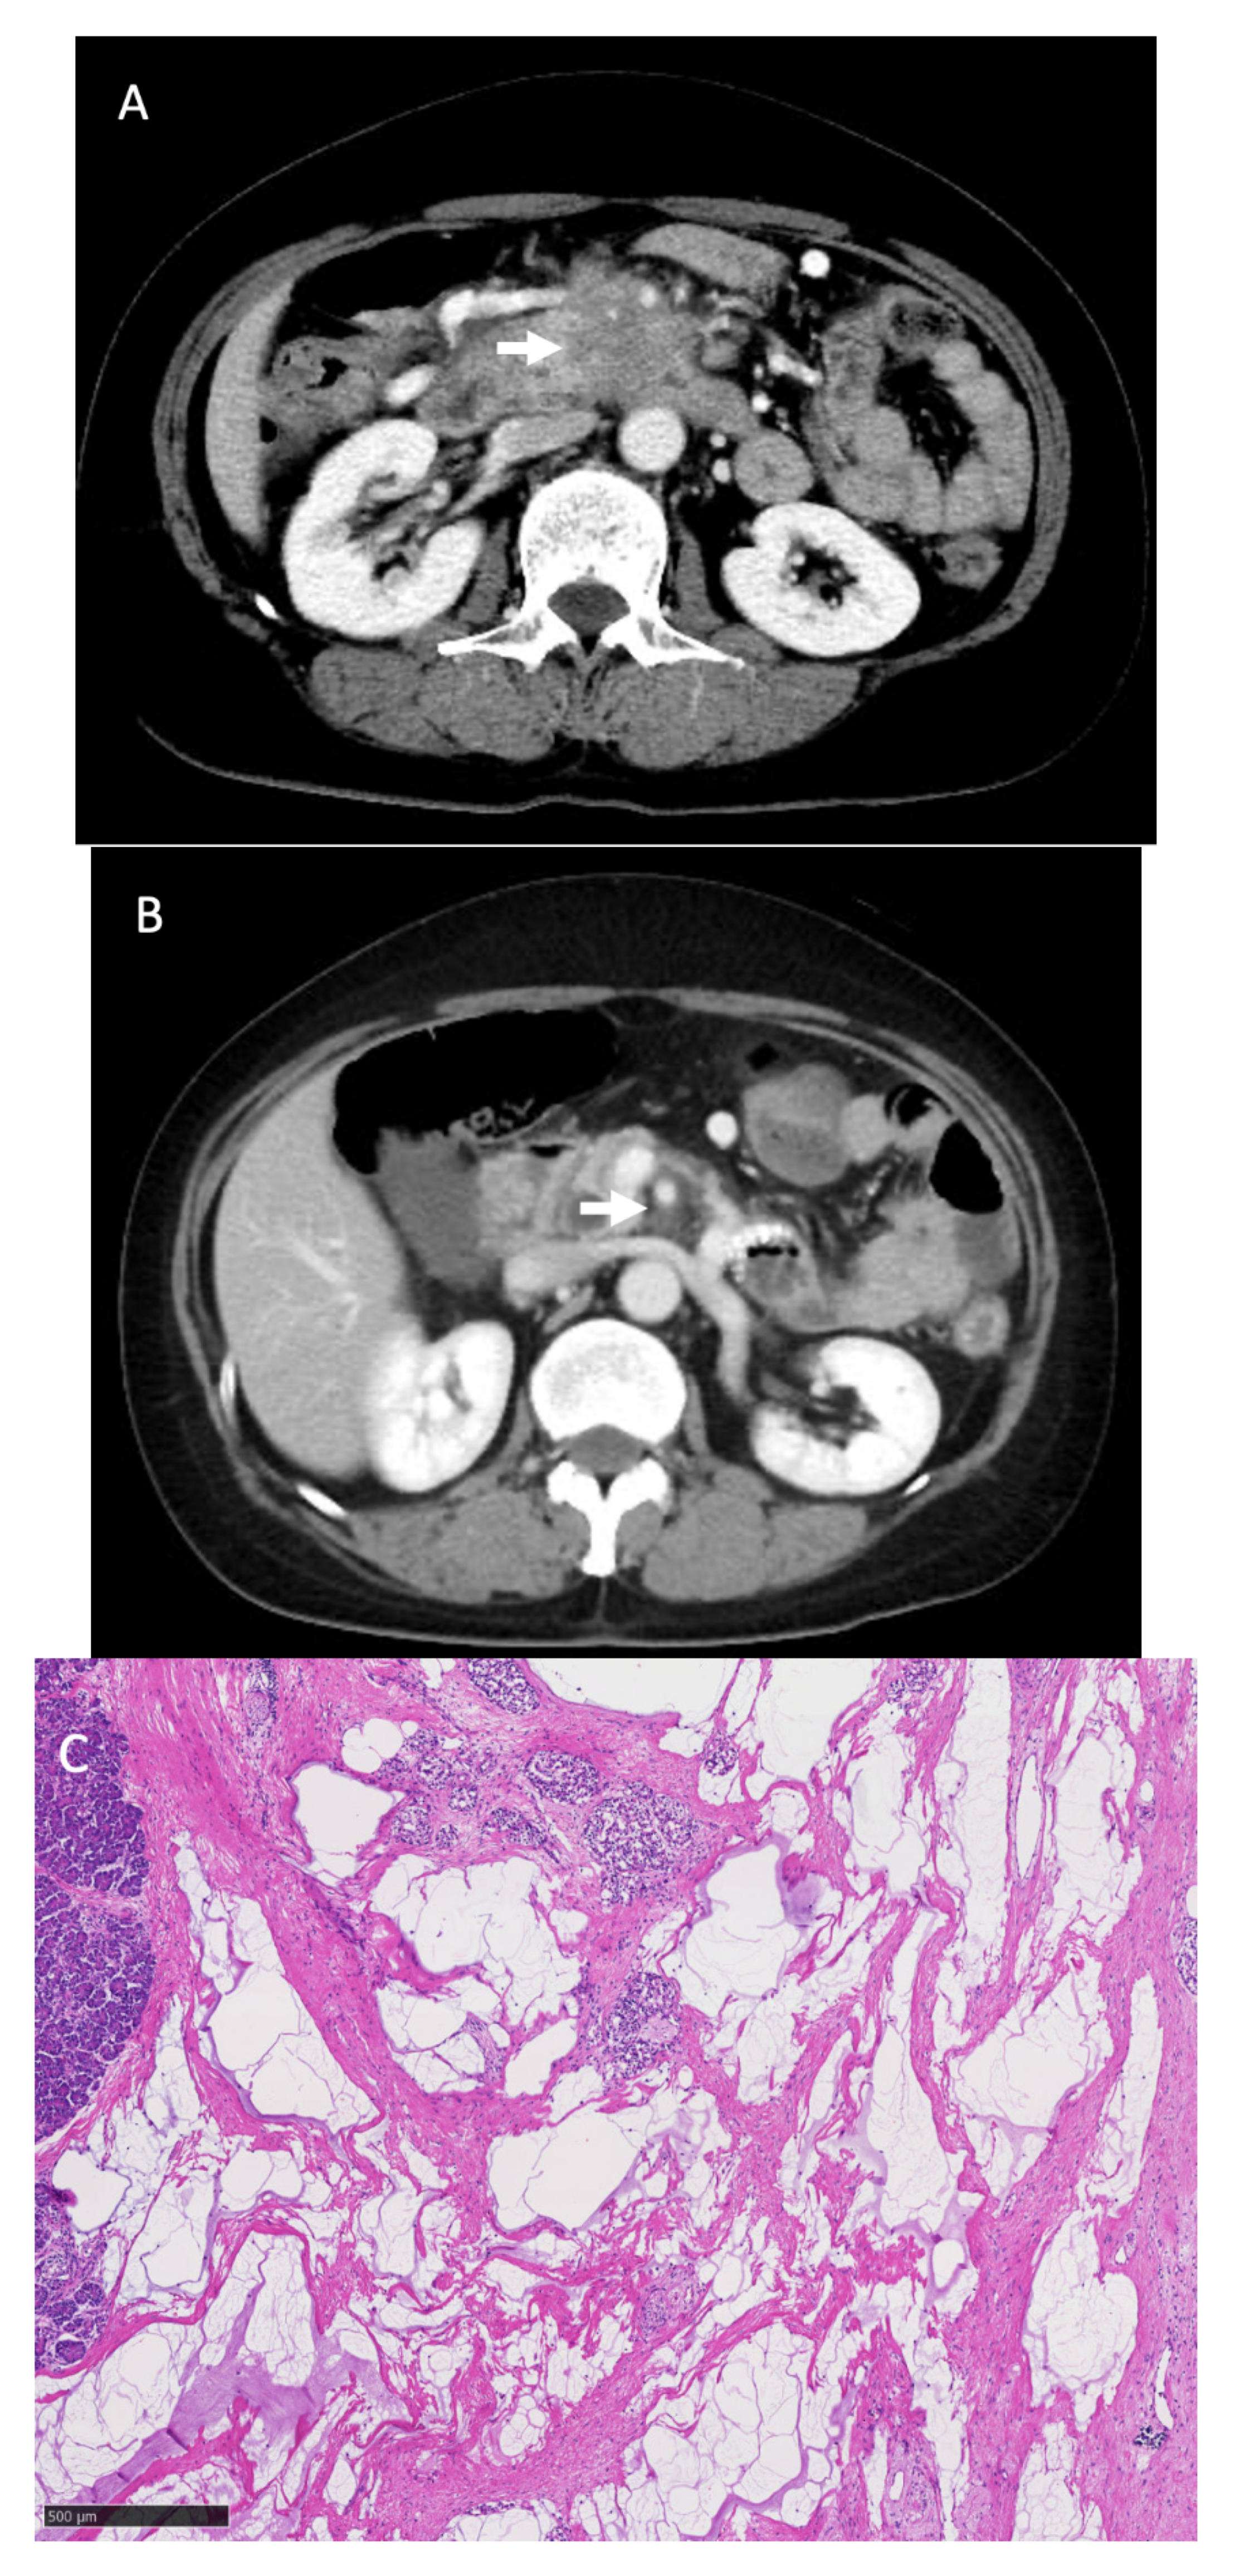

| Patient No. | Duration (Months) (Cycles) | Treatment Effect (RECIST) | Adverse Events (≥Grade 3) | CA19–9(U/mL) Peak/after Chemotherapy | Relative Dose Intensity (%) | Findings of Unresectable Factor | ||||

|---|---|---|---|---|---|---|---|---|---|---|

| L-OHP | CPT-11 | 5-FU | LV | |||||||

| 1 | 7.1 (10) | PR | Neutropenia G4 | 6529 / 32 | 42.9 | 56.2 | 68.1 | 68.1 | M (HEP/Multi) | disappeared |

| 2 | 8.0 (13) | PR | Peripheral sensory neuropathy G3 | 1462 / 55 | 59.6 | 74.5 | 85.0 | 85.0 | LA (SMV) | disappeared |

| 3 | 23.9 (47) | PR | Neutropenia G3 | 250 / 13 | 65.1 | 79.8 | 86.8 | 87.7 | M (PER/Multi) | disappeared |

| 4 | 23.3 (31) | PR | Neutropenia G4 | 4379 / 81 | 42.8 | 56.4 | 69.9 | 68 | M (HEP/Multi) | disappeared |

| 5 | 6.8 (11) | PR | Neutropenia G4 | 171 / 12 | 71.8 | 81.4 | 83.4 | 83.0 | LA (Ao) | disappeared |

| 6 | 13.3 (27) | PR | Neutropenia G4 | 5431 / 20 | 60.9 | 89.7 | 92.7 | 92.2 | LA (SMA, SMV) | improved |

| 7 | 4.5 (6) | PR | Neutropenia G3 | 370 / 177 | 50.2 | 53.3 | 65 | 66 | M (PER/Multi) | disappeared |

| 8 | 24.0 (36) | PR | Neutropenia G4 | 10424 / 27 | 41.7 | 56.5 | 65.7 | 66.4 | M (HEP/Multi) | disappeared |

| Patient No. | Operative Procedure | Operative Time (min) | Blood Loss (ml) | Major Complications | Hospital Stay (Days) | pTNM | Residual Tumor | Tumor Viability (Evans) |

|---|---|---|---|---|---|---|---|---|

| 1 | DP | 220 | 100 | - | 20 | pT2N0M0, stageIB | R0 | IIb |

| 2 | PD | 520 | 710 | - | 50 | pT2N1M0, stageIIB | R0 | IIb |

| 3 | DP | 445 | 1840 | - | 22 | pT3N0M0, stageIIA | R0 | IIa |

| 4 | DP | 350 | 290 | - | 19 | pT3N0M0, stageIIA | R0 | IIb |

| 5 | PD | 500 | 685 | - | 31 | pT3N0M0, stageIIA | R0 | IIb |

| 6 | PD | 880 | 1790 | GDA pseudoaneurysm rupture Pancreatic fistula | 47 | pCR | R0 | IV |

| 7 | DP-CAR | 360 | 330 | - | 15 | pT3N1M0, stageIIB | R0 | IIb |

| 8 | PD | 430 | 610 | Chylous ascites | 41 | pCR | R0 | IV |